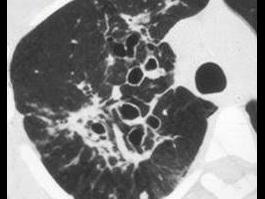

女,28岁,反复咯血半月余,CT检查如图,选出最可能的诊断 ( )A、支气管扩张B、肺脓肿C、肺癌D、间质性肺炎E、肺结核

问题 女,28岁,反复咯血半月余,CT检查如图,选出最可能的诊断 ( )

选项 A、支气管扩张 B、肺脓肿 C、肺癌 D、间质性肺炎 E、肺结核

答案 A